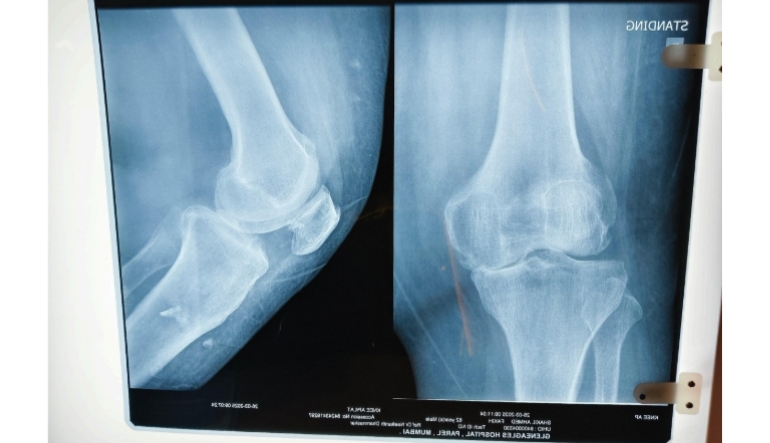

Knee pain can occur due to multiple reasons, and identifying the exact cause is essential for effective treatment.

● Osteoarthritis and age-related joint wear

● Ligament injuries such as ACL or MCL strain

● Meniscus injuries

● Patellofemoral pain syndrome